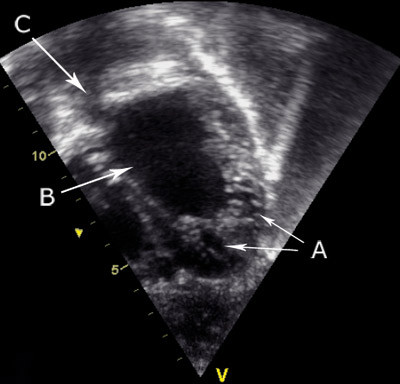

Ved ekkokardiografi fant man normalt beliggende firekammerhjerte med normale systemforbindelser og lungevenøse forbindelser, normalt klaffeapparat, intakt atrie- og ventrikkelseptum og normale forhold ved lungearterie og aorta. Det var forstørret høyre hjertehalvdel med stort, struttende høyre atrium med septum bukende inn i venstre. Høyre ventrikkel var dilatert og hypertrofisk med en trikuspidalinsuffisiens på ca. 4 m/s, som uttrykk for pulmonal hypertensjon. Venstre ventrikkels kavitet fremsto som liten. Begge ventrikler hadde generelt nedsatt kontraktilitet. Man startet digitalisering.

Neste dag var den kliniske tilstanden bedre, og jenta ble overflyttet til regionsykehus for videre utredning. Sviktterapien ble supplert med furosemid og kaptopril, og det var vedvarende klinisk bedring og normalisering av biokjemiske variabler. Det ble gjort ny ekkokardiografi, der de beskrevne funnene ble verifisert. I tillegg bemerket man hypertrofe, trabekulerte ventrikler og lite ventrikkellumen. På bakgrunn av dette stilte man diagnosen manglende modning av ventrikkelmyokard (ventricular non-compaction).

Diagnostiske hjelpemidler ved hjertesvikt hos barn omfatter røntgen thorax, EKG-undersøkelse og særlig ekkokardiografi for å avdekke årsaken til og ev. graden av hjertesvikt. Forhøyet nivå av NT-proBNP i blodet taler for hemodynamisk belastning og/eller hjertesvikt og har særlig klinisk anvendelighet ved vurdering av graden av hjertesvikt og effekten av behandling. Referanseintervallet for NT-proBNP er avhengig av målemetoden og pasientens alder. Serumnivået er høyest de første levedøgn, med etterfølgende raskt fall i løpet av den første levemåned. Heretter følger en svakt fallende tendens resten av barndommen (3). Man må være klar over denne fysiologiske utviklingen når prøven gjentas, spesielt det første leveåret. Hos vår pasient viste ekkokardiografi betydelig nedsatt kontraktilitet av begge ventrikler, dilatert høyre hjertehalvdel, økt lungekarmotstand og hypertrofe, trabekulerte ventrikler med nedsatt ventrikkellumen. Hjertesviktdiagnosen ble understøttet av kardiomegali på røntgen thorax, forhøyet NT-proBNP og høyresidig belastningsmønster på EKG.